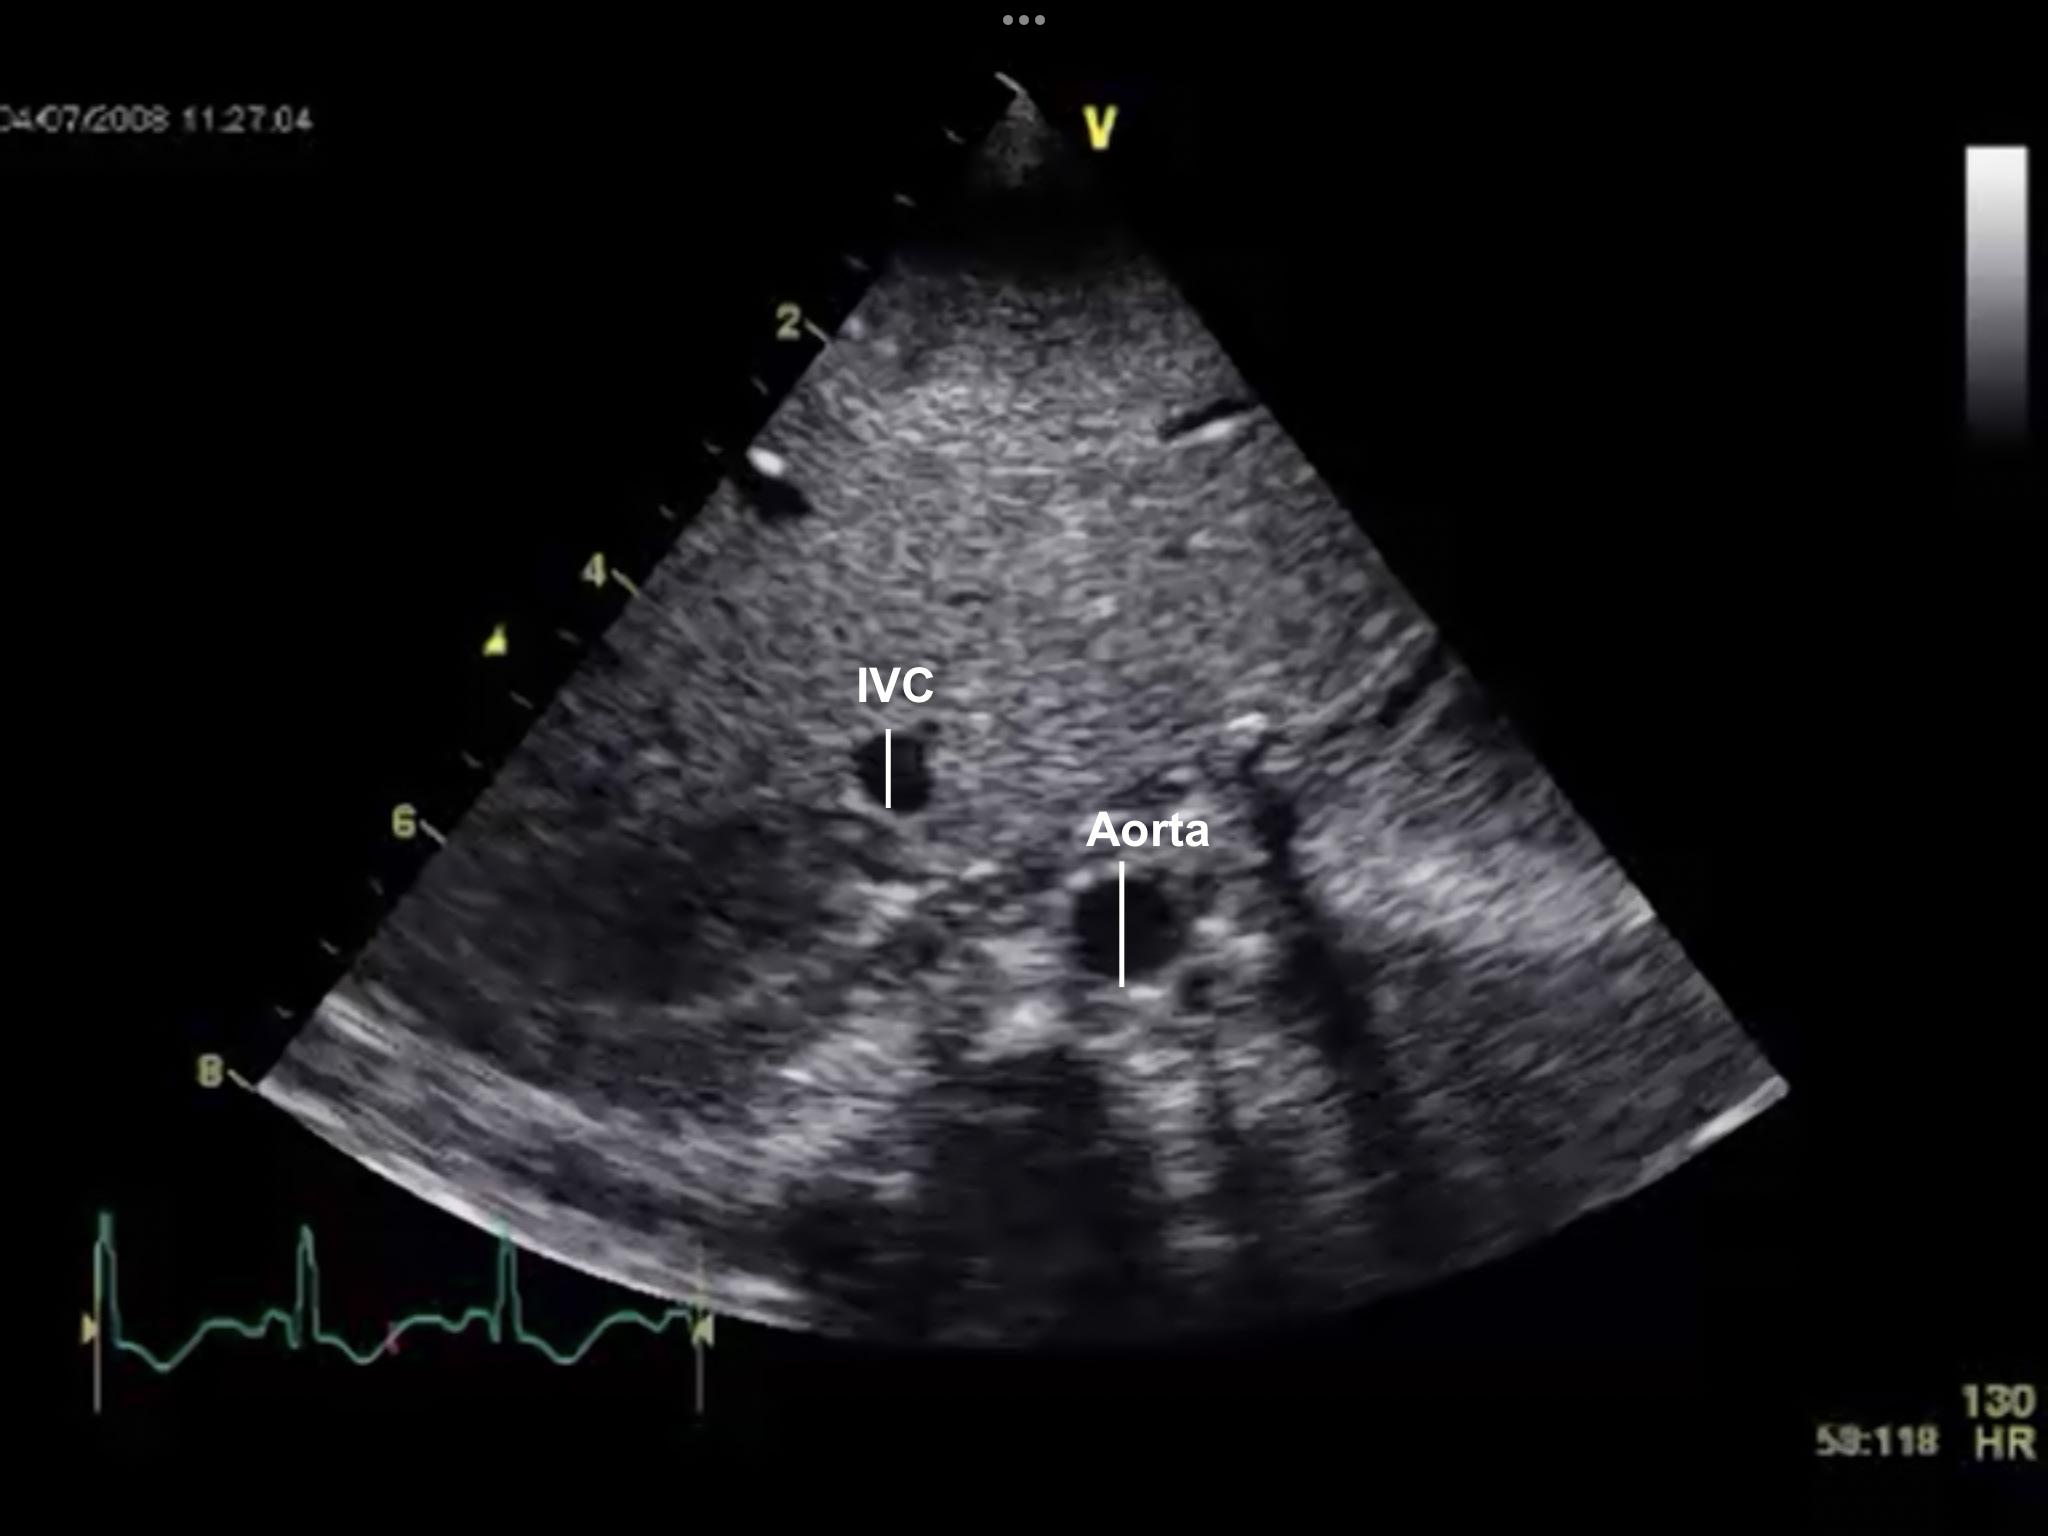

Not Just Small Adults: Tailoring Point-of-Care Ultrasound Skills for Pediatric Patients

Point-of-Care Ultrasound in Acute Monocular Vision Loss